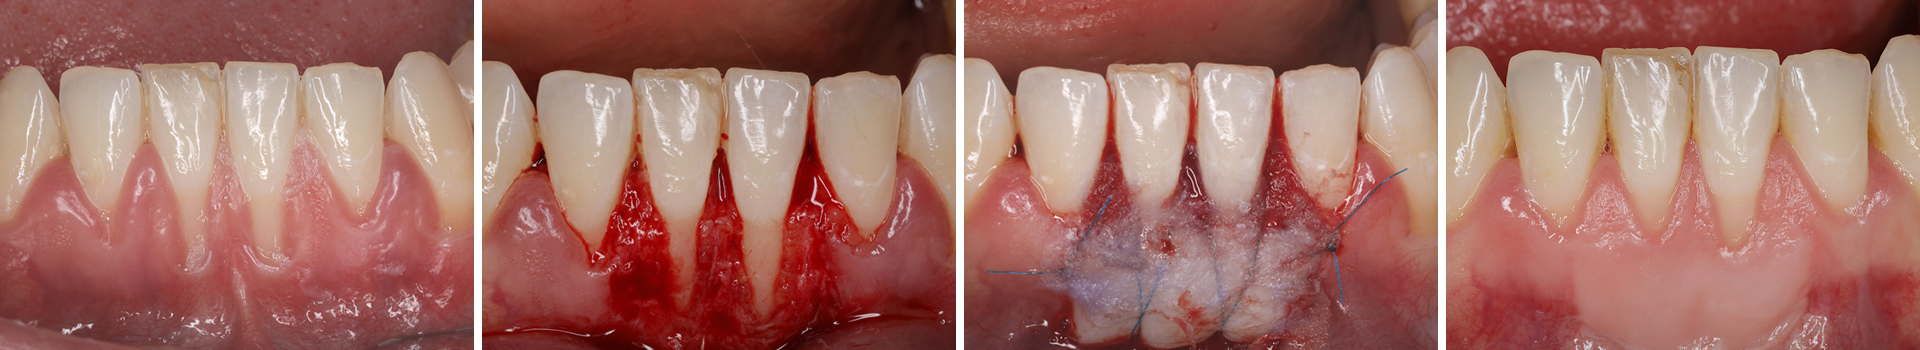

Abbildung 2

Präparation des Empfängerbetts für die Aufnahme eines freien Schleimhauttransplantates.

Abbildung 3

Fixation des FST mit Kreuz- und Einzelkopfnähten.

Abbildung 4

Abdeckung des Transplantates mit PeriAcryl® 90-HV Gewebekleber.

Abbildung 5

Klinische Situation 13 Monate nach Weichgewebsaugmentation.